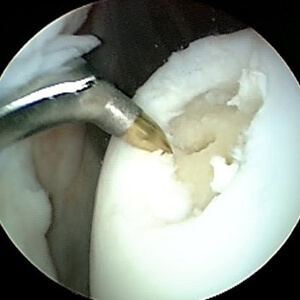

Several factors must be considered to decide to treat joint cartilage injury: surface area, depth, location, history, associated injuries, knee stability, meniscal injuries, mechanical limbs, patient age, and last but not least functional characteristics of the patient. MRI examination, Outerbridge Classification, ICRS Assessment System are very useful for choosing the therapeutic method. Regarding the repair of cartilage lesions along with the entire thickness, several treatments have been suggested, but none have been identified as the "gold standard" to allow the reproduction of normal hyaline joint tissue. One of the first treatments is simple abrasive chondroplasty when the cartilaginous defect is "shaved" and subjected to extensive debridement.

Washing and Debridement of articular cartilage

These arthroscopic techniques have proven useful for patients with reduced mechanical stress on the joint and unique and relatively small lesions on the surface and who do not wish to undergo long-term recovery treatment. The results obtained are relatively low by the isolated use of this method. These are techniques performed in an arthroscopy, along with other surgical techniques.